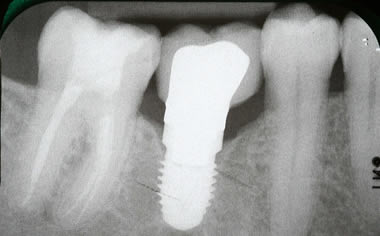

More back teeth replaced by dental implants

Case Five (4 images)